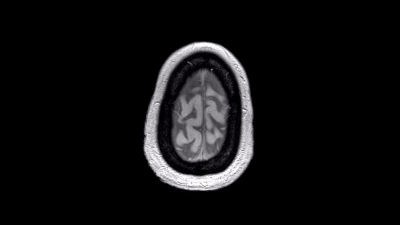

Beroende - Ett psykedeliskt botemedel?

+Genom hjärnröntgen har man upptäckt att kontrollerade narkotikarus kan hjälpa missbrukare, tillräckligt för att bryta ett beroende?